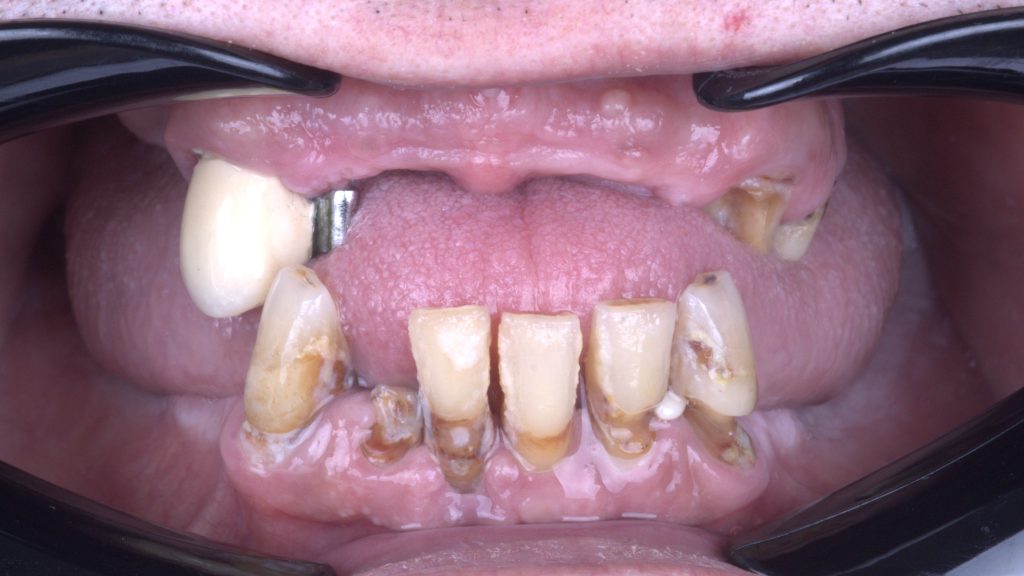

INITIAL STATE

Terminal dentition.

Remaining teeth are inadequate for future restoration